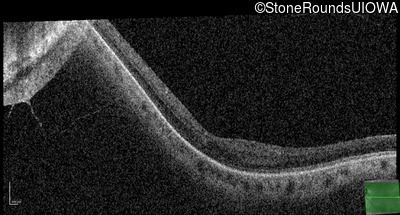

Age at visit: 41 years (Visit 2)

OD OS

This 41 year old woman was highly myopic as a child and experienced a rhegmatogenous retinal detachment OS at age 20.

Refraction OD:     -17.25 +1.00 x 93

Refraction OS:     -18.25 +3.50 x 56